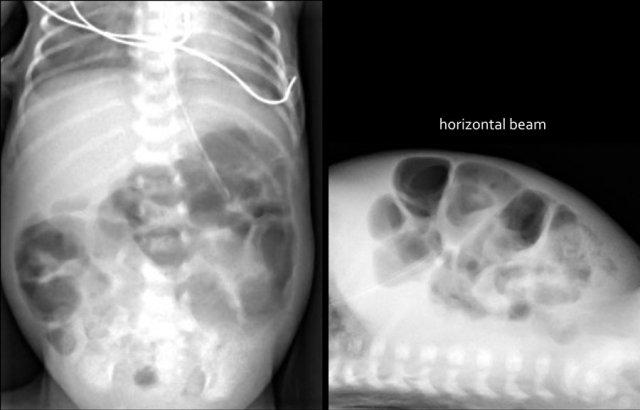

Đây là một trường hợp điển hình khác của viêm ruột hoại tử.

Lưu ý hình ảnh khí trong tĩnh mạch cửa (mũi tên) và các nhánh tĩnh mạch cửa ngoại vi.

Dấu hiệu này được thấy trên X-quang và siêu âm.

Ở bệnh nhân viêm ruột hoại tử này, hãy chú ý các bóng khí trong thành ruột và trong nhu mô gan.